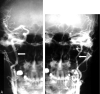

Background and purpose: Two large trials indicated that endarterectomy was less beneficial for symptomatic patients with internal carotid artery (ICA) near occlusion than for patients who had severe stenosis without near occlusion. Near occlusions complicate ratio calculations of ICA stenosis and require attention to detail for identification. The goal is to provide diagnostic criteria, illustrate identifying features, estimate accuracy of identification, and assess prognosis for patients with near occlusion.

Methods: We re-reviewed 1216 patients with severe (> or =70%) stenosis on angiography in the North American Symptomatic Carotid Endarterectomy Trial and European Carotid Surgery Trial. One of 5 (n = 262) had 2 or more criteria for near occlusion: (1) delayed cranial arrival of ICA contrast compared with external carotid artery (ECA); (2) intracranial collaterals seen as cross-filling of contralateral vessels or ipsilateral contrast dilution; (3) obvious diameter reduction of ICA compared with opposite ICA; or (4) ICA diameter reduction compared with ipsilateral ECA.